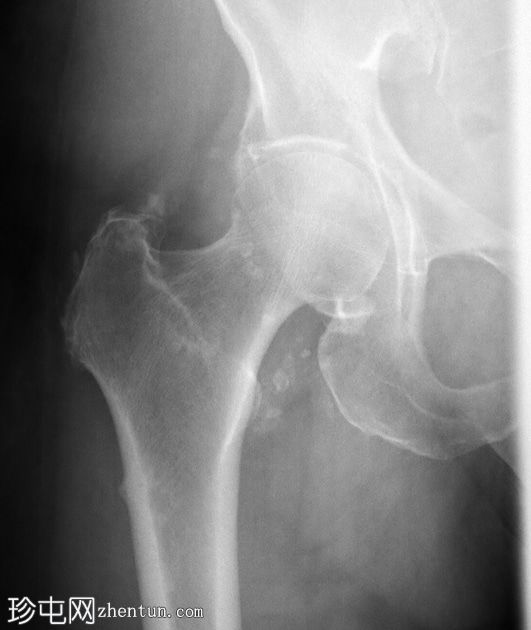

MRI

冠状位

T1

一条水平T1和T2低信号骨折线横断右股骨干外侧皮质。近1/3的骨干周长受累,并伴有邻近骨髓水肿。其余皮质骨完整。左股骨未见异常。